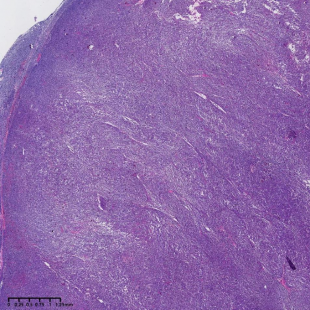

图1:低倍镜下,淋巴结正常结构破坏,淋巴样细胞弥漫分布,局部呈结节状,可见瘤细胞侵犯淋巴结被膜。